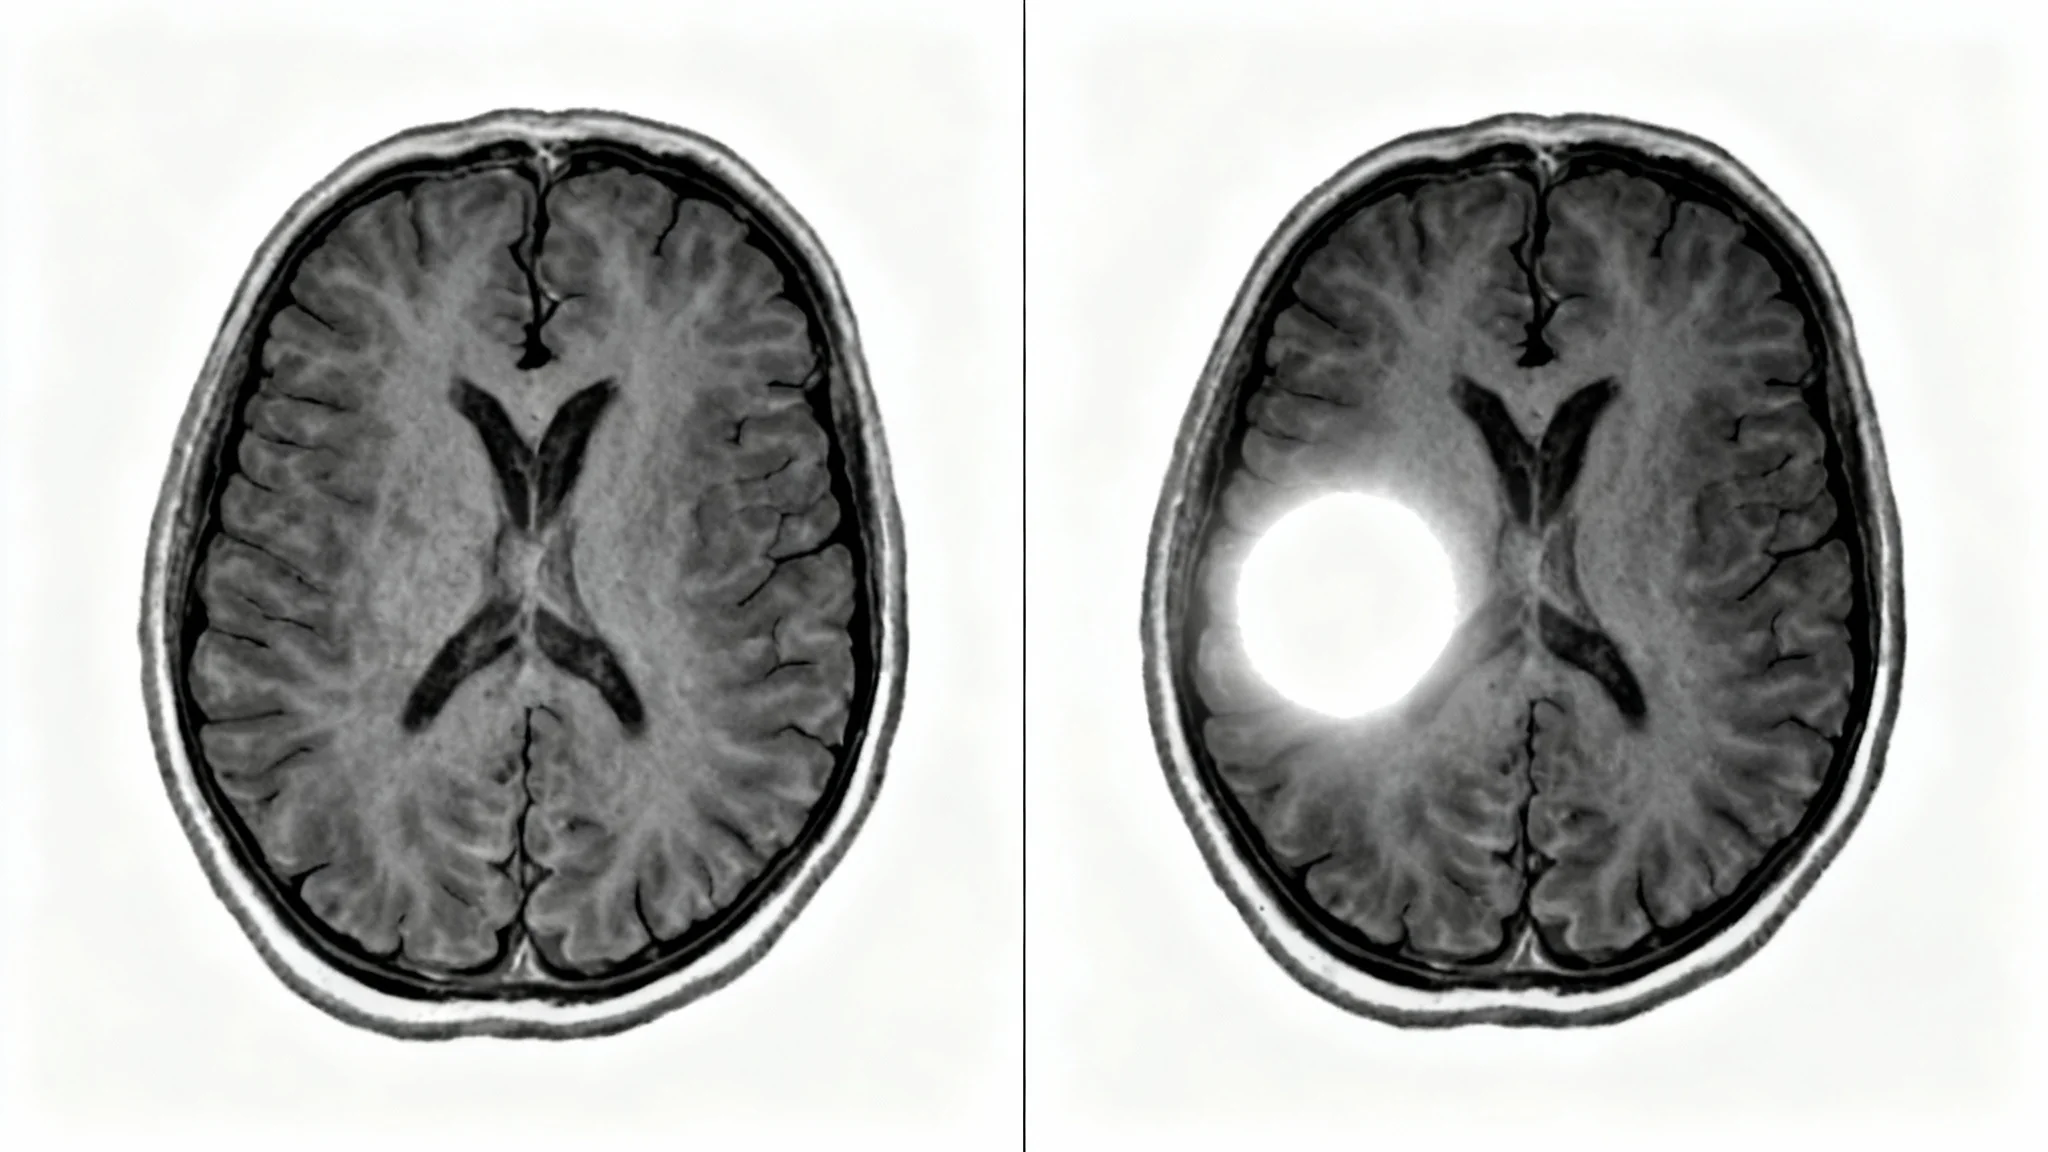

A side-by-side comparison of two MRI brain scans. The left scan is a standard grayscale image, while the right scan shows the same view with contrast enhancement, making a specific lesion glow brightly.

Neuro-Oncology: Improve the visualization of brain tumors to better assess their boundaries, internal structure, and relationship to adjacent tissues. Musculoskeletal (MSK) Imaging: Enhance the visibility of inflammation in joints, soft tissue lesions, and subtle bone marrow abnormalities. Cardiovascular MRI: Sharpen the delineation of myocardial tissue to aid in the assessment of viability and scarring. Oncological Imaging: Assist in the characterization of lesions in organs like the liver or kidneys by clarifying enhancement patterns. Clinical Research: Generate consistently enhanced images for quantitative analysis in research studies.